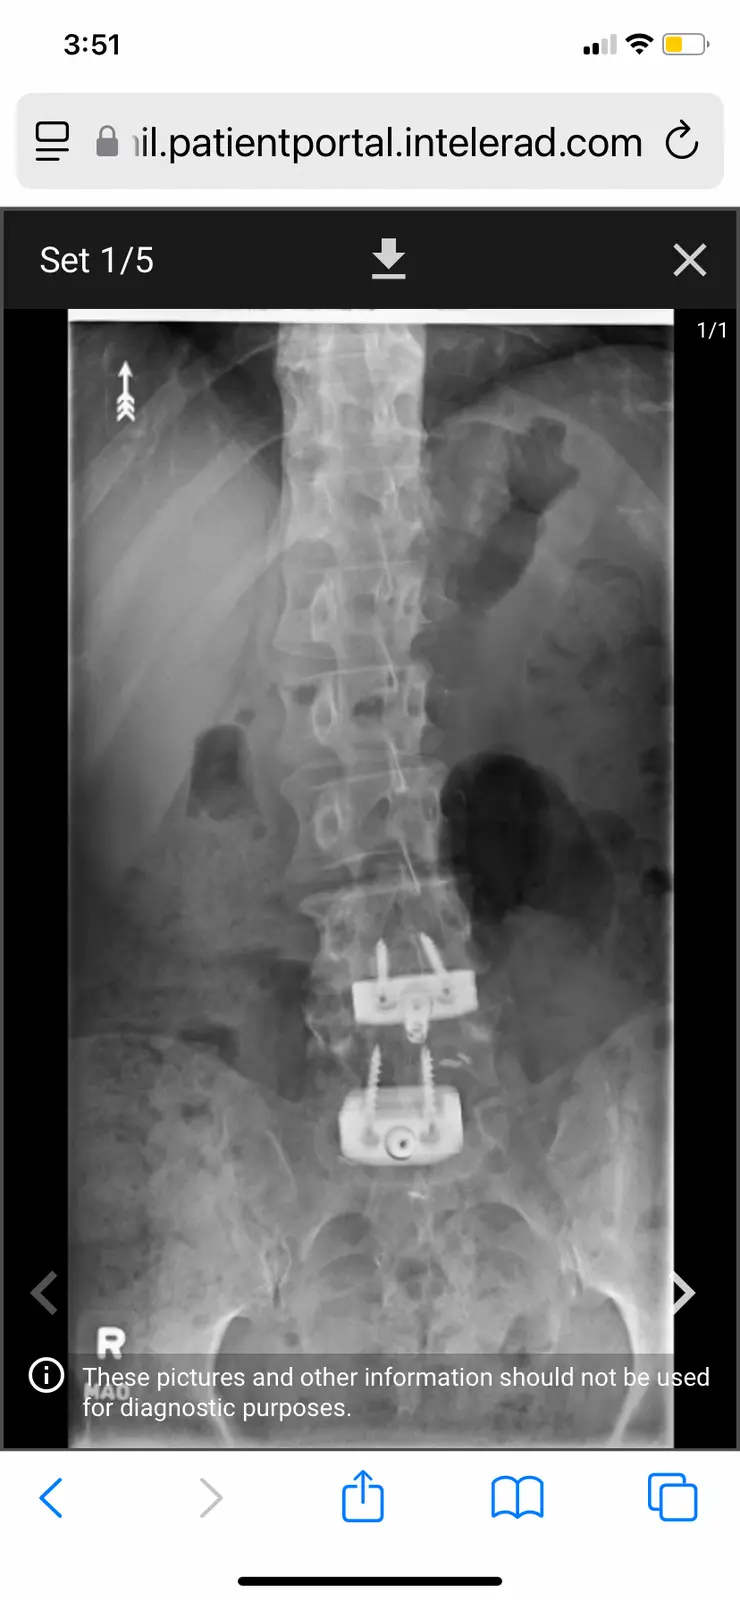

i had this surgery on the 19th of march. Im doing pretty goodl Im 75